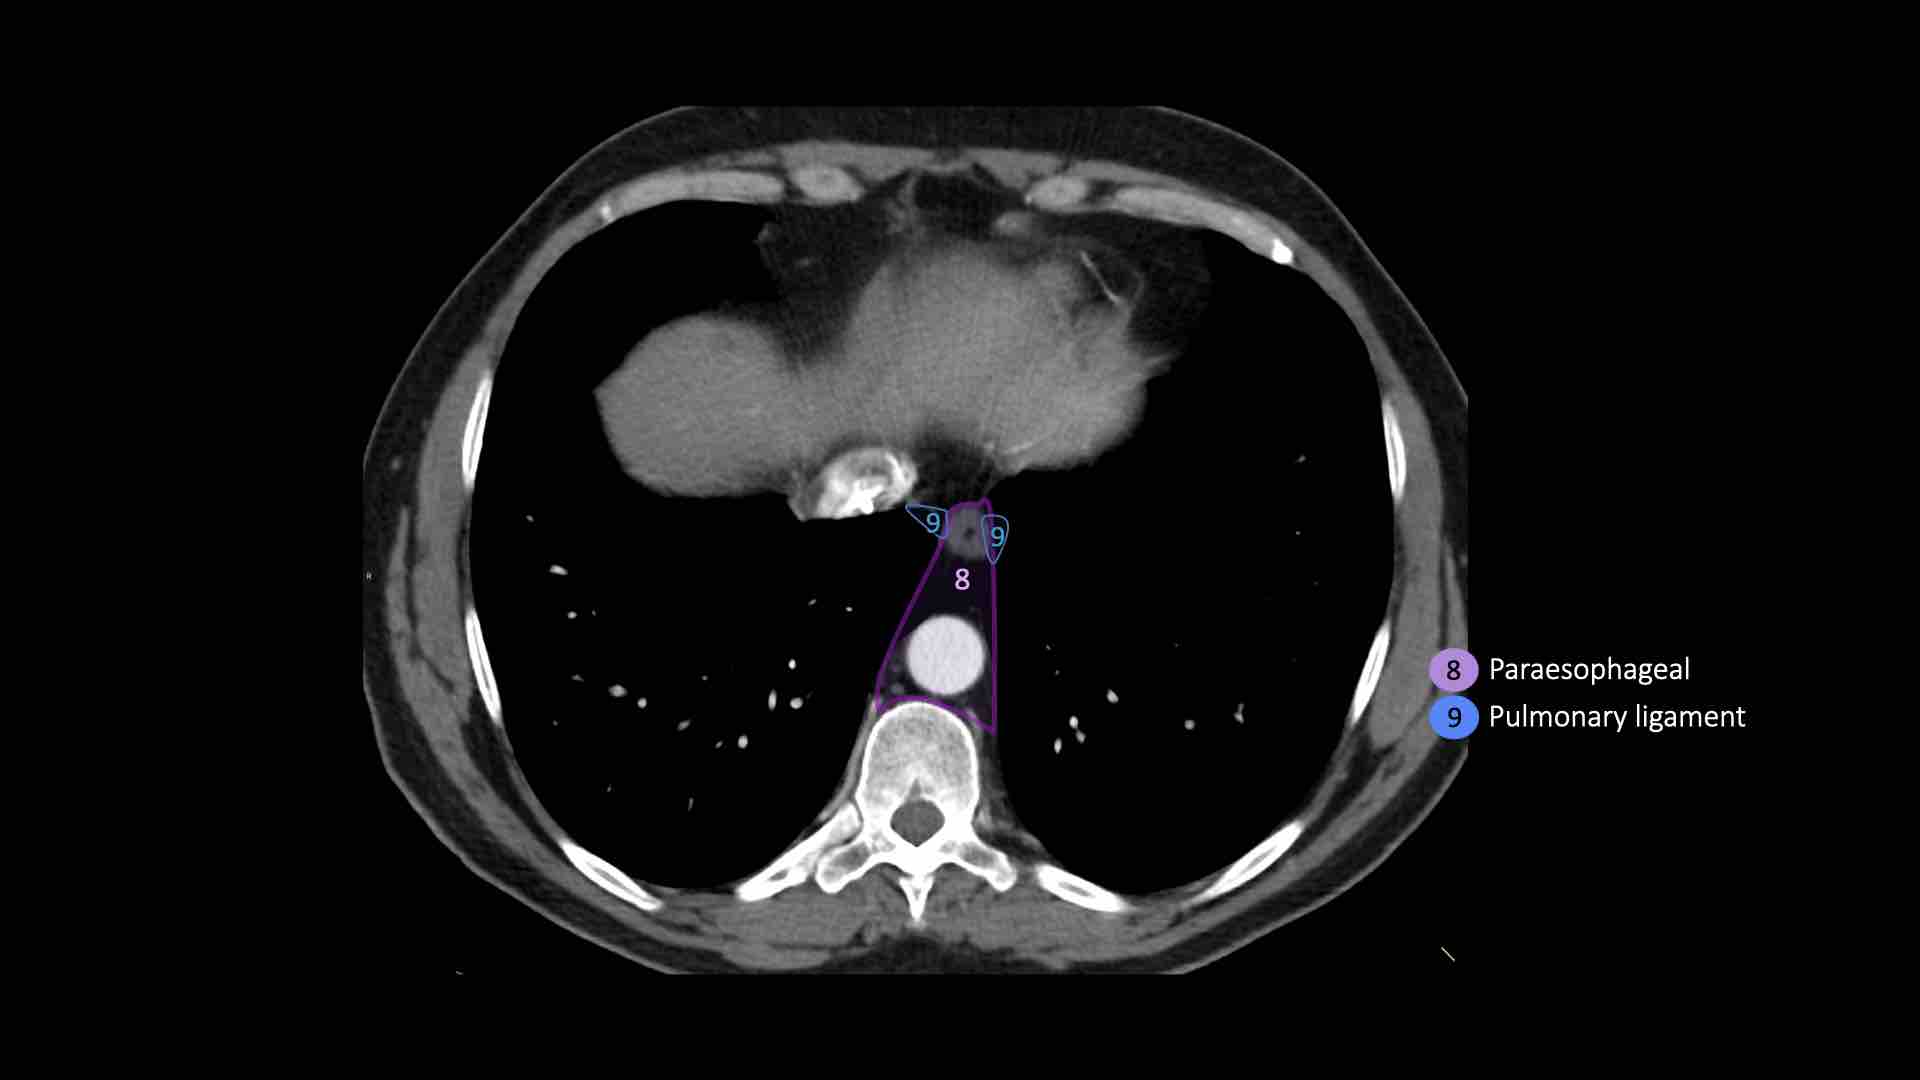

8. Cạnh thực quản

Các hạch nằm dưới carina.

9. Dây chằng phổi

Các hạch nằm trong dây chằng phổi.

8. Hạch cạnh thực quản

Các hạch này nằm bên dưới các hạch dưới carina và trải dài xuống đến cơ hoành.

9. Hạch dây chằng phổi

Hạch dây chằng phổi nằm trong dây chằng phổi, bao gồm các hạch ở thành sau và phần dưới của tĩnh mạch phổi dưới.

Dây chằng phổi là phần kéo dài xuống dưới của các nếp gấp màng phổi trung thất bao quanh rốn phổi.